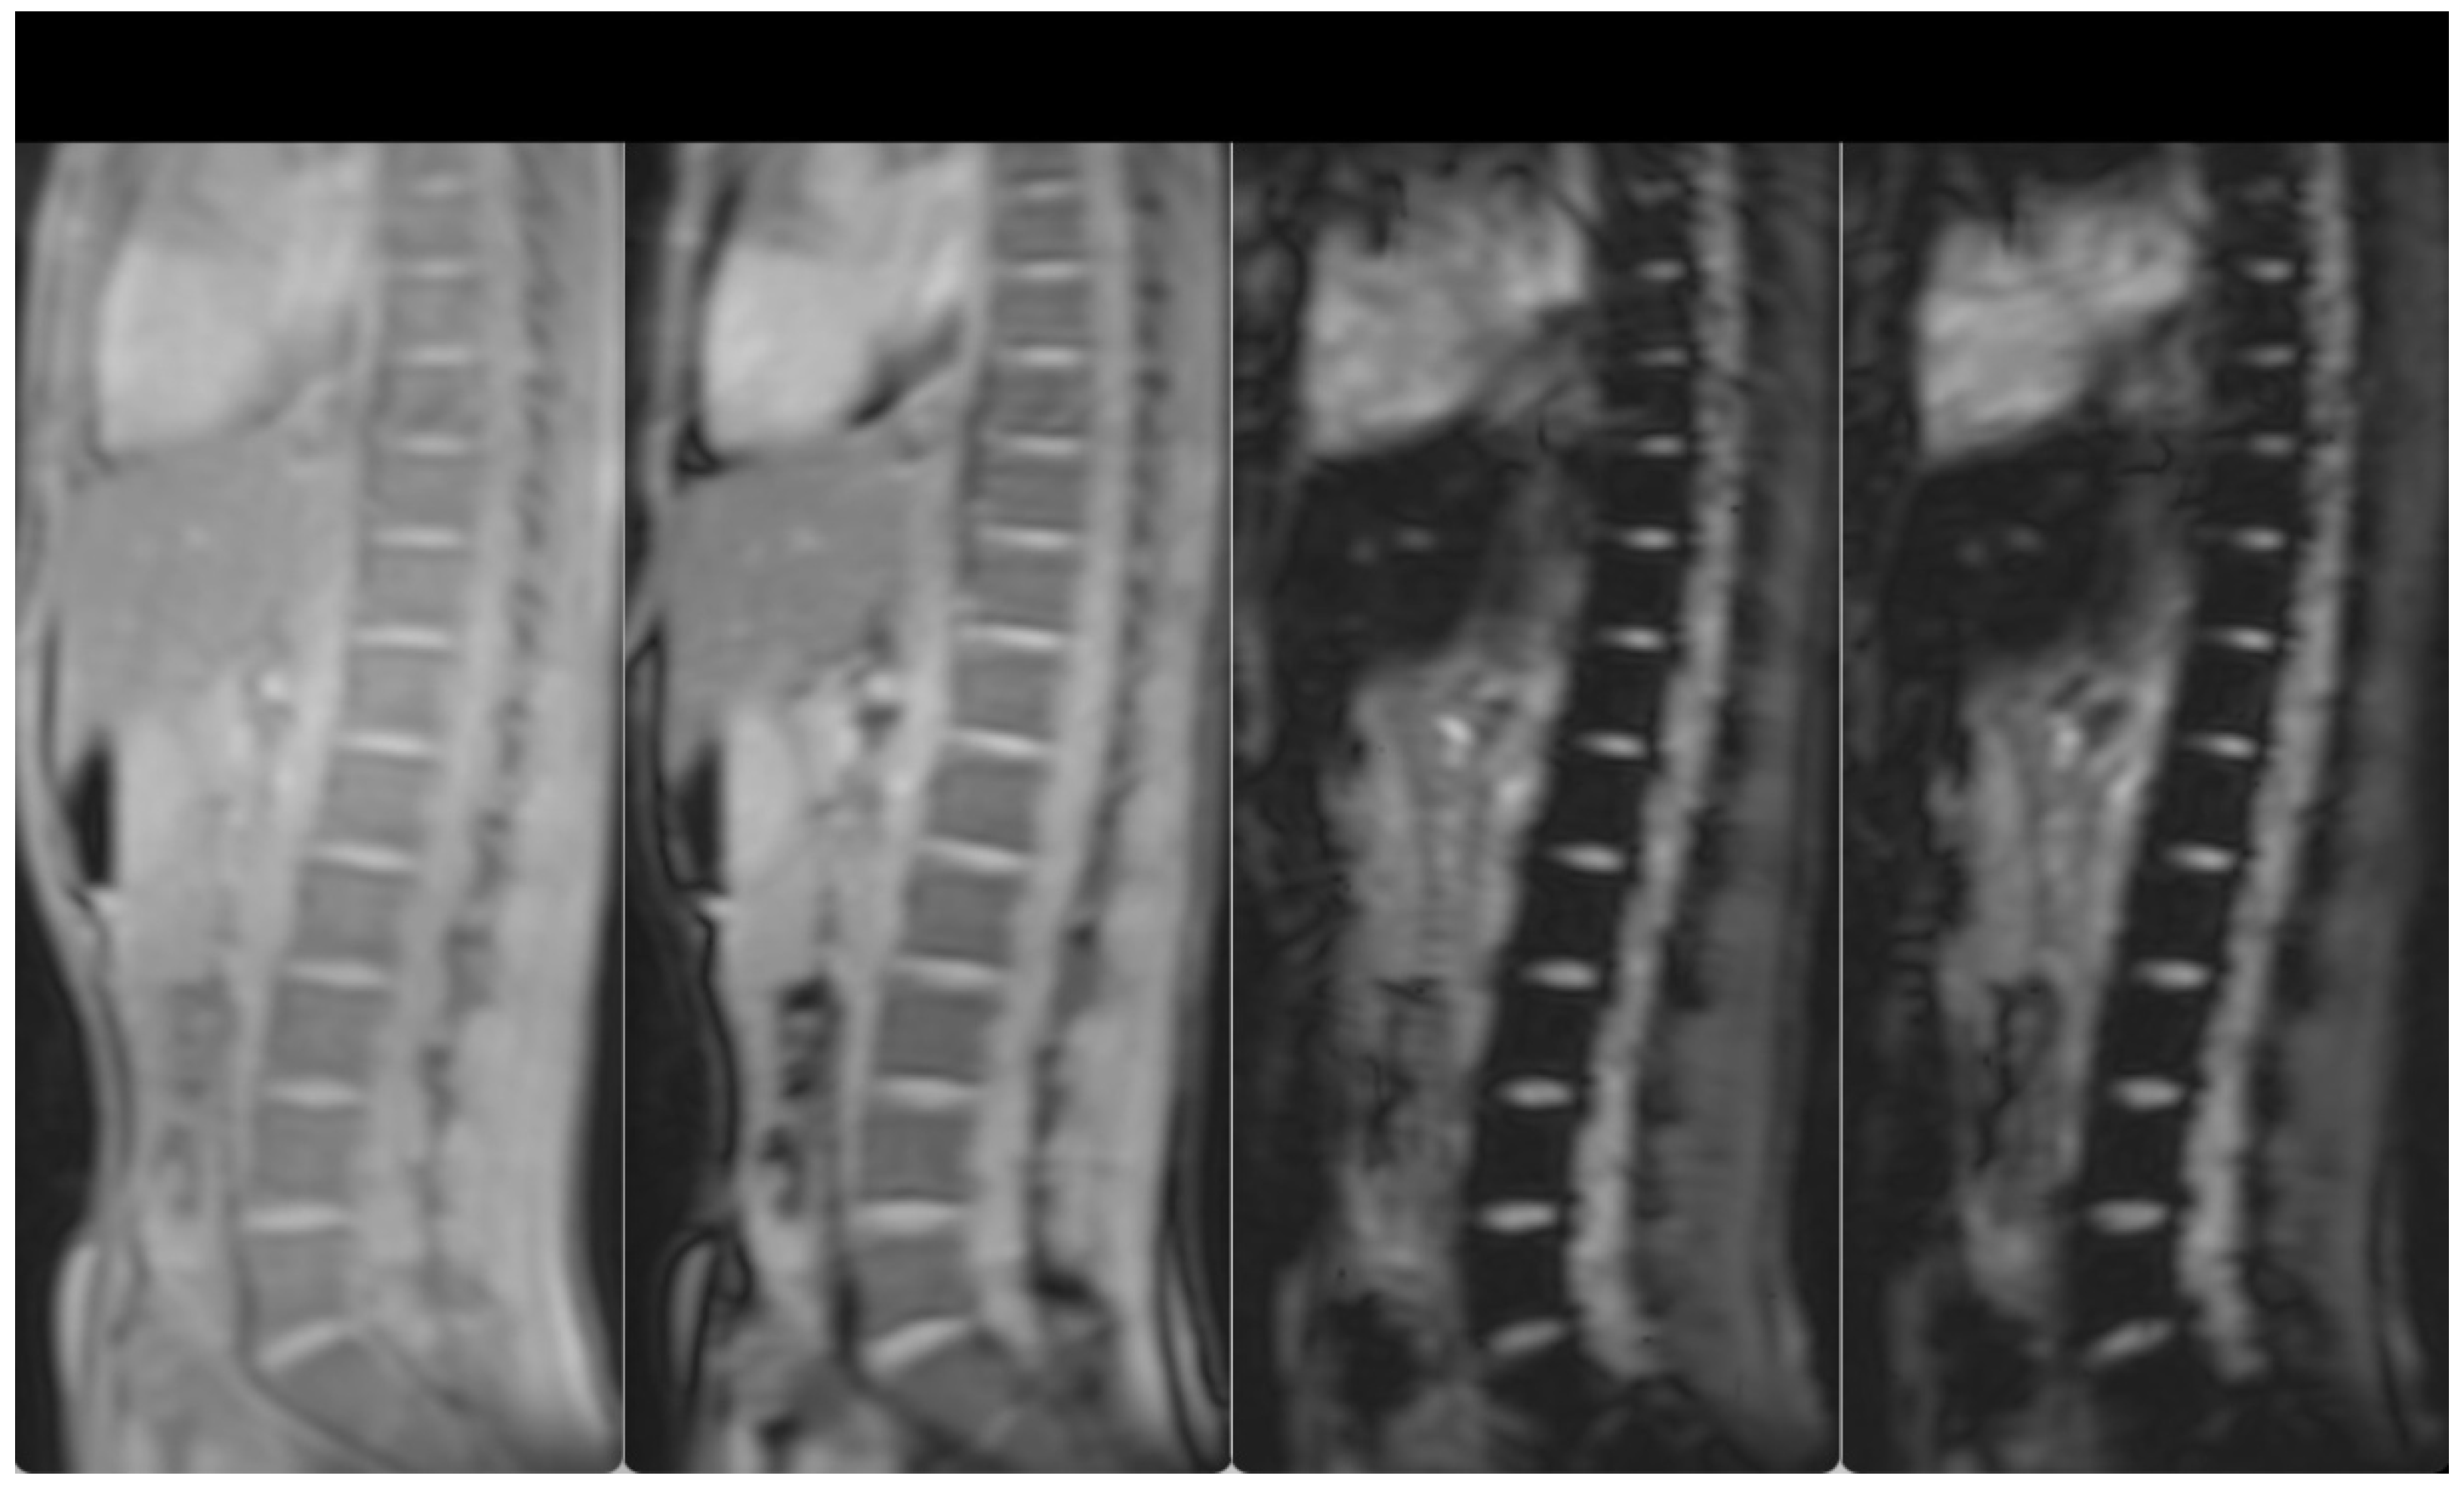

3. Case Presentation